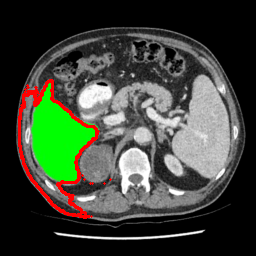

| U-Net | nnU-Net | TransU-Net | SAM-PP-0 | SAM-PP-5 |

| SAM-PP-50 | SAM-PP-100 | SAM-Mix-5 | SAM-Mix-50 | SAM-Mix-100 |

Our primary findings comparing the proposed model to baseline fully-supervised models when segmenting the liver from the LiTS dataset are reported in Table 1. The reported results demonstrate that our SAM-Mix model consistently achieves higher Dice scores compared to the fully supervised baselines as well as the two-stage SAM-PP method. Against U-Net, the best-performing fully supervised method, the SAM-Mix variant trained on 50 segmentation labeled slices (SAM-Mix-50), achieves a Dice score improvement of 5.9%. In terms of Hausdorff distance, while the fully-supervised baselines do slightly outperform SAM-Mix-5 and SAM-Mix-100, SAM-Mix-50 does achieve a lower Hausdorff distance by 22.38%. Qualitative evaluation as shown in Figs. 3 further affirms the superiority of SAM-Mix over baseline and existing fully-supervised methods as well as the two-stage SAM-PP variants. Furthermore, the boxplot visualization in Fig. 2 showcases consistently improved performance by SAM-Mix outperforming all the fully supervised and semi-supervised methods.